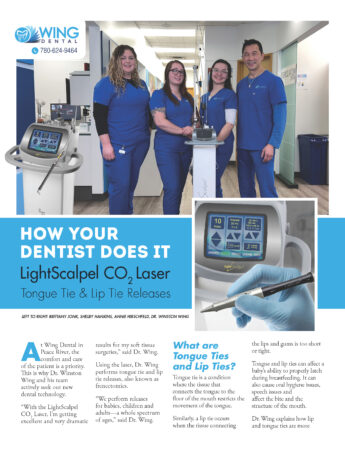

Wing Dental Adopts New Technology for Comfortable and Effective Frenectomy Procedures

Dr. Winston Wing, a customer of LightScalpel, recently published an excellent article in a local magazine. In the article, he discusses the frenectomy procedure and explores the numerous applications and benefits of the LightScalpel CO2 laser.

Wing Dental in Peace River, AB, prioritizes the comfort and well-being of its patients, which is why Dr.